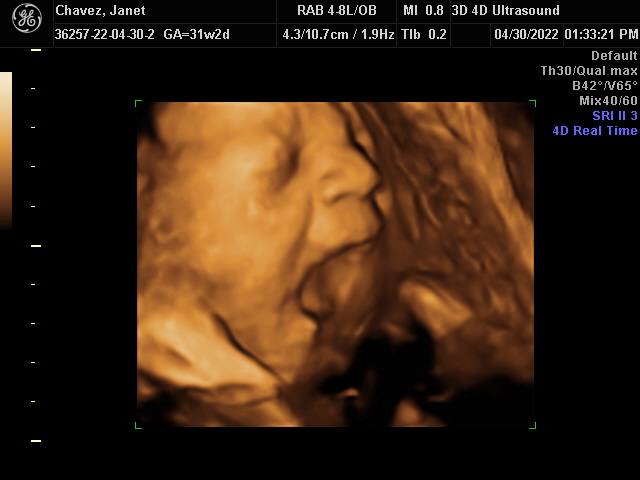

Our Gallery

Explore beautiful moments captured during our 3D and 4D sessions.